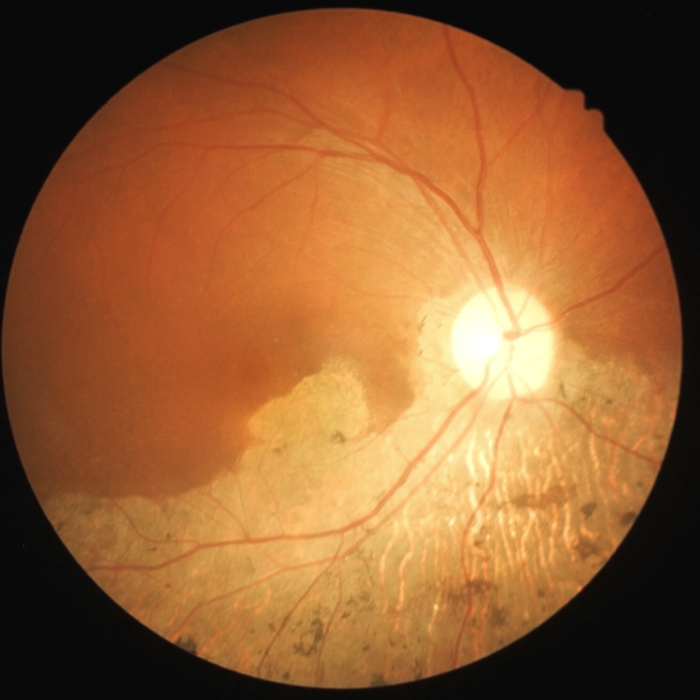

Retina Orange County Macular Degeneration Harvard Eye What Is Amd In The Eyes It happens when a part of the retina called the macula is damaged. Amd is the most common cause of severe loss of eyesight among people ages 60 and older. The two types of amd. It damages the macula and the retina, leading to. It ultimately leads to central vision loss, which. It happens when aging causes damage. What Is Amd In The Eyes.